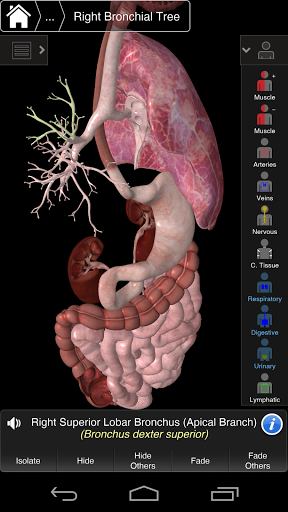

⁃Oddechowy

⁃Trawienny

Essential Anatomy 3 jest responsywny, wizualnie oszałamiający i pozbawiony wysiłku. Aplikacja jest w pełni 3D, co oznacza, że możesz zobaczyć dowolną strukturę anatomiczną w izolacji, a także pod dowolnym kątem.

Mądra funkcjonalność znajdująca się w aplikacji pozwala użytkownikowi usunąć warstwy mięśni za pomocą narzędzia "skalpela". Ta aplikacja zapewnia użytkownikom możliwość włączania / wyłączania systemów bez potrzeby wyłączania poszczególnych struktur lub pomieszania wielu predefiniowanych kart regionalnych, tak jak w przypadku innych aplikacji.

---- Ponad 4000 bardzo szczegółowych struktur anatomicznych

---- Tryb wielokrotnego wyboru - Ukryj / Zniknij / Izoluj pojedyncze lub wiele struktur

---- Prawidłowa wymowa audio dla każdej struktury

---- nomenklatura łacińska dla każdej struktury anatomicznej